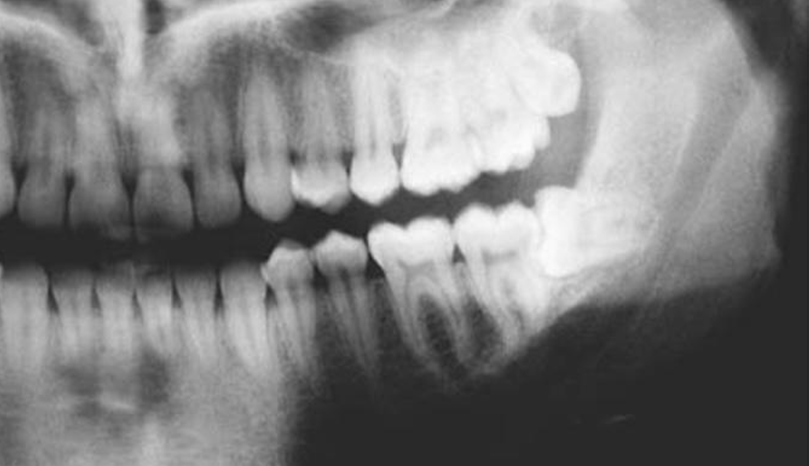

Dalam menangani impaksi gigi bungsu perlu dilakukan pemeriksaan yang menyeluruh oleh dokter gigi spesialis bedah mulut. Pemeriksaan yang dilakukan seperti pemeriksaan klinis yang mencakup ekstra oral dan intra oral serta pemeriksaan radiografik yaitu pemeriksaan panoramik atau biasa disebut foto dental. Berdasarkan hasil panoramik dokter gigi spesialis bedah mulut dapat memprediksi gigi tersebut akan mampu erupsi sempurna atau tidak, dan merencanakan tatalaksana sesuai indikasi. Tatalaksana dapat berupa tindakan dengan pembedahan atau tanpa pembedahan. Untuk tindakan pembedahan dinamakan Odontektomie yaitu prosedur pembedahan dengan cara pengangkatan gigi impaksi.